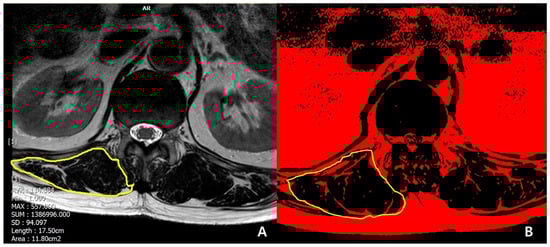

- Lee, J.C.; Cha, J.G.; Kim, Y.; Kim, Y.I.; Shin, B.J. Quantitative analysis of back muscle degeneration in the patients with the degenerative lumbar flat back using a digital image analysis: Comparison with the normal controls. Spine 2008, 33, 318–325. [Google Scholar] [CrossRef] [PubMed]

| Muscular quantity of T12-L1 (CSA of erector spinae), cm2 | 23.8 ± 4.2 | 32.2 ± 10.1 | <0.001 * |

| Muscular quality of T12-L1 (Fat infiltration in CSA of erector spinae) | <0.001 * | ||

| Mild to moderate (<50%), n | 4 | 21 | |

| Severe (≥50%), n | 13 | 3 | |

| Muscle quality of T12-L1 (Fat infiltration in CSA of erector spinae) | 0.002 * | 43.60 | 4.11–463.06 |